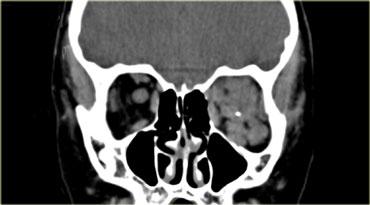

Bên nào bất thường và chẩn đoán có khả năng nhất là gì?Có hình ảnh thiểu sản cánh xương bướm bên phải và bên trái thần kinh thị giác gần giao thoa thị giác bị phì đại (thấy rõ trên MRI).

Do đó chẩn đoán là bệnh u xơ thần kinh type I (NF-1) với thiểu sản cánh xương bướm và u thần kinh đệm đường thị giác.Thuật ngữ “u thần kinh đệm thị giác” thực ra không hoàn toàn chính xác.